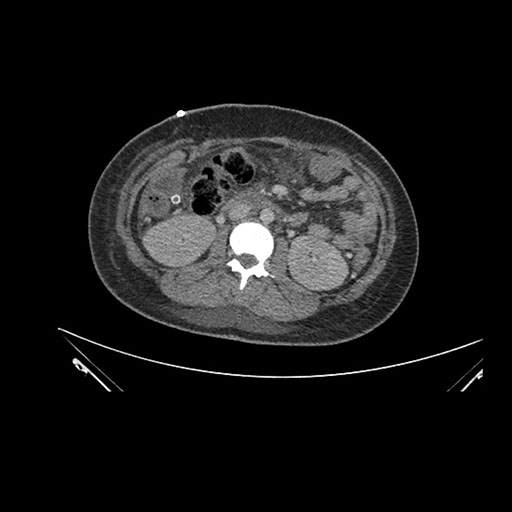

Axial Arterial